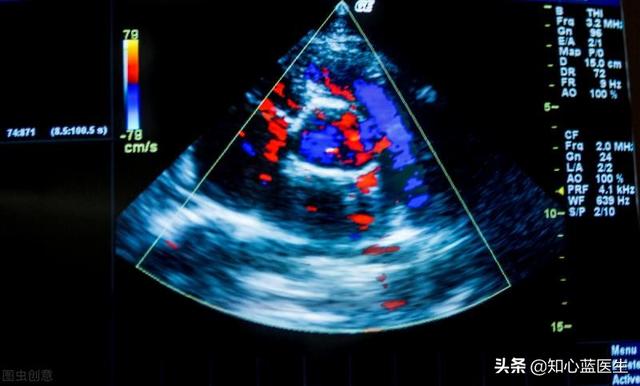

心臓超音波検査は、心臓の大きさ、可動性、収縮力を測定する定規のようなものである。

- 心臓超音波は音波の原理に基づいている。心臓から反射された音波を受信し、心臓超音波検査装置で画像に変換することで、心臓の個々の心房と心室の大きさ、心臓の収縮力、弁の状態、心臓の活動を直接測定することができる。しかし、心臓超音波検査では通常、冠動脈の狭窄や閉塞を直接見ることはできない。

- 重度の心筋虚血冠動脈疾患、あるいは比較的大きな心筋梗塞は、心臓超音波検査で心収縮力の変化としてはっきりと確認することができる。心筋活動の変化、さらには心臓弁の機能異常も見られる。このようにして、心筋が重度の虚血に陥っていることが間接的に推測できる。

5.心臓超音波

心臓超音波検査は心臓の構造の変化を反映するもので、心臓の収縮・拡張機能が正常かどうか、駆出率が正常かどうかに加えて、心房や心室の壁の破損や肥厚の有無、心房や心室の肥大の有無、心臓の弁の狭窄や閉鎖不全の有無などを反映することができます。